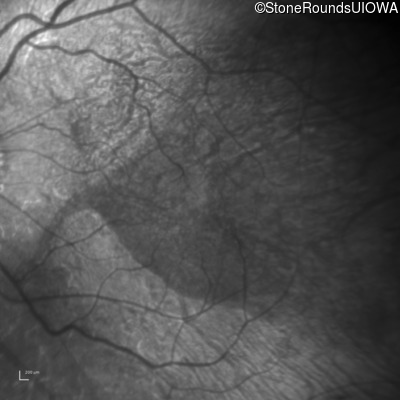

This 30 year old woman has had poor vision in her right eye for her entire life and first noticed decreased vision in dim light and constricted fields in her left eye in middle school. She had surgery in infancy for "short gut syndrome" and had liver transplantation at age 3. She also has a history of pulmonary stenosis, scoliosis, and ataxia.

| Alagille Syndrome | JAG1 | Gly193del1tatG | AD |